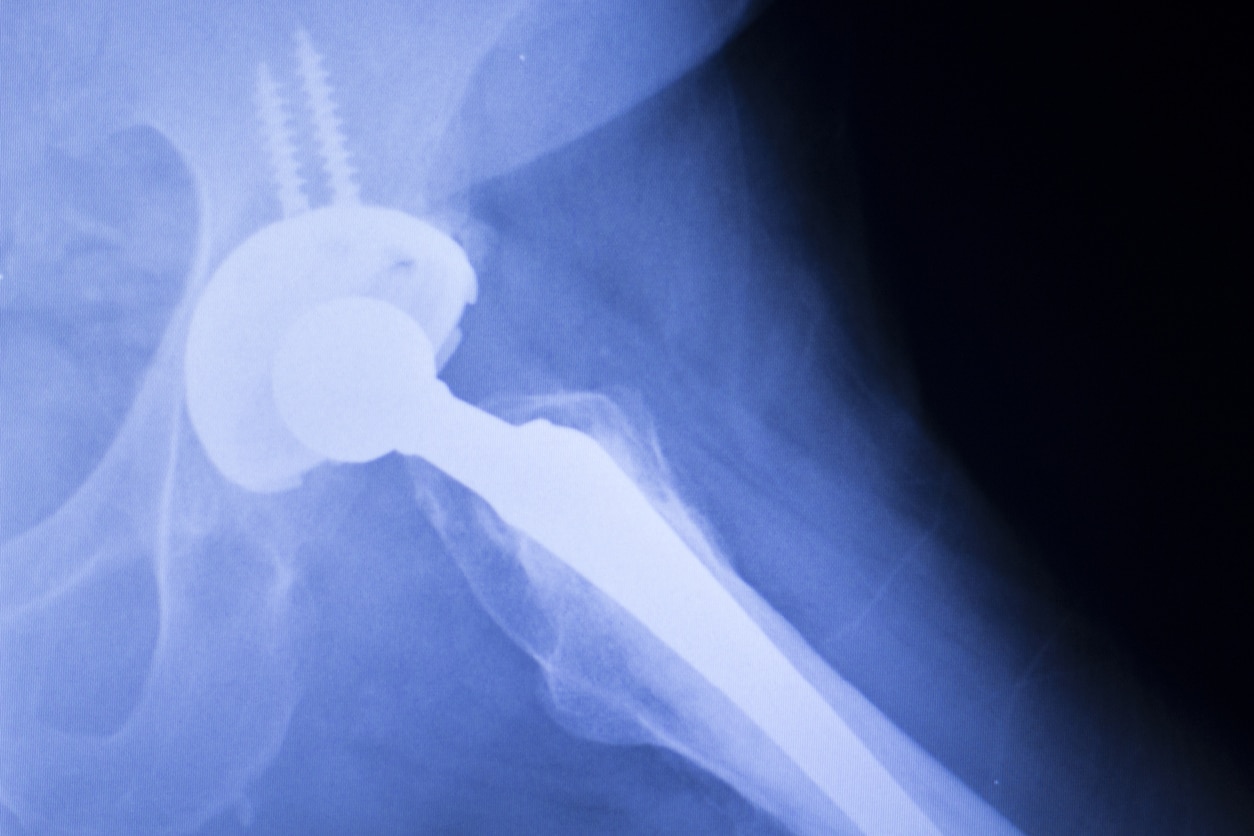

Wright Medical Technology Inc. manufactures the Conserve, a metal-on-metal implant used in total hip replacement surgery. The Conserve is designed with an all-metal “ball-and-socket” design, in which a metal femoral head that pivots inside a metal acetabular cup. It was approved with a 510(k) application, which allows manufacturers to introduce new devices without conducting safety studies so long as it is “substantially equivalent” to another product already on the market.

Most claims allege that the metal-on-metal design of the Wright Conserve is defective because it generates high levels of metal debris, causing metallosis (metal poisoning) in the surrounding tissue. Local tissue reactions can include pain, swelling, inflammation, soft-tissue growths (pseudo-tumors), bone loss, and tissue death. According to the FDA, metallosis can also cause systemic reactions in other areas of the body. These side effects can lead to premature failure (including loosening of the acetabular cup) and require revision surgery.